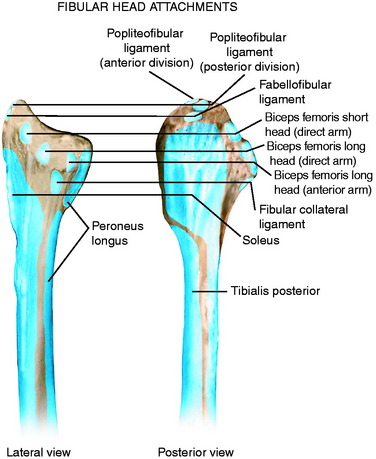

Анатомия фибулы: Подробные фотографии и схемы

:background_color(FFFFFF):format(jpeg)/images/article/fibula/zQsPkIKgm2DJTfO5rTKh6g_Fibula_and_knee_joint.png)